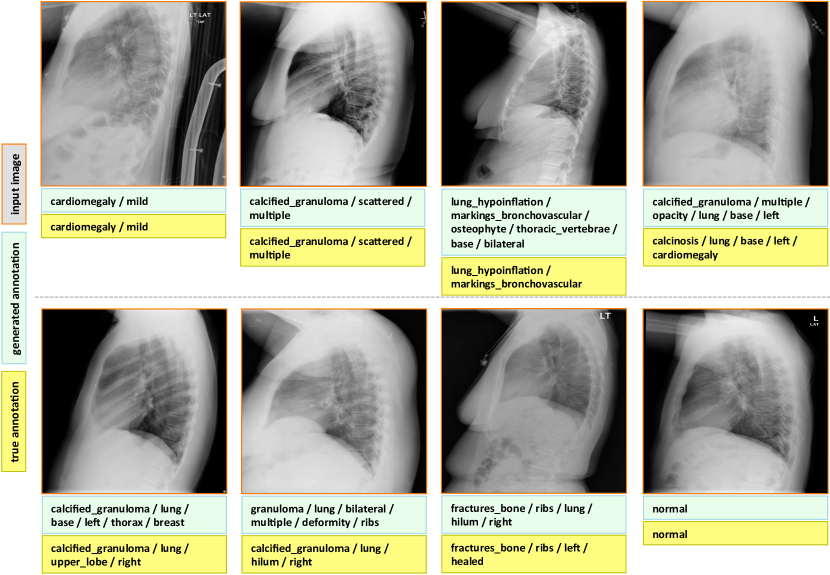

Appendix C More Annotation Generation Examples

More annotation generation examples are provided in Figures 10 and 11. Overall, the system generates promising results on predicting disease (labels) and its context (attributes) in the images. However, rare disease cases are more difficult to detect. For example, the cases pulmonary_atelectasis, spondylosis, and density (Figure 10), as well as foreign_bodies, atherosclerosis, costophrenic_angle, deformity (Figure 11) are much rarer in the data than calcified_granuloma, cardiomegaly, and all the frequent cases listed in Table 1 of the main paper.

Furthermore, the (left or right) location of the disease cannot be identified in a lateral view (obtained by scanning the patient from the side), as shown in Figure 11. Since our dataset contains a limited number of disease cases, we treat each x-ray image and report as a sample, and do not account for different views.